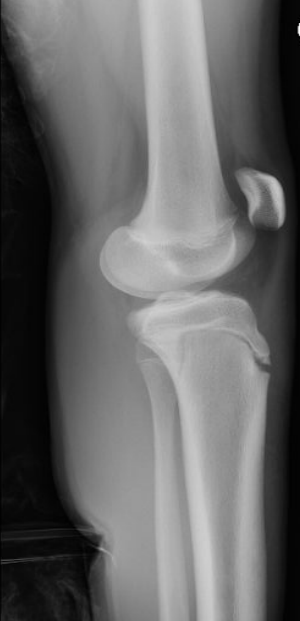

Orthopedics Gepost op 4 maart 20194 maart 2019 door netwerkvsseh Board Review: Orthopedics @emdaily.cooperhealth.org Dit delen: Delen op X (Opent in een nieuw venster) X Share op Facebook (Opent in een nieuw venster) Facebook Delen op LinkedIn (Opent in een nieuw venster) LinkedIn E-mail een link naar een vriend (Opent in een nieuw venster) E-mail Afdrukken (Opent in een nieuw venster) Print Vind-ik-leuk Aan het laden... Gerelateerd